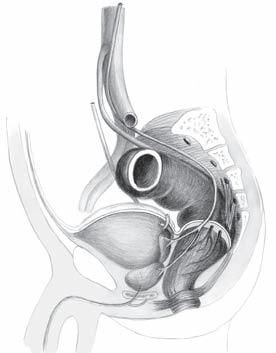

2.3 Chirurgická topografie malé pánve

Znalost topografických vztahů rekta k okolním orgánům v malé pánvi je předpokladem přesné preparace při operaci (obr. 2.6). Anatomické poměry v oblasti rekta, které je uloženo intraperitoneálně, jsou peroperačně většinou vizuálně přehledné. Po mobilizaci sigmoidea lze spolehlivě v retroperitoneu určit průběh levého močovodu, vasa ovarica či spermatica, průběh vasa iliaca communis a v oblasti promontoria plexus hypogastricus. Následná retroperitoneální mobilizace mezosigmoidea přes střední čáru (orientace podle aorty a páteře) umožní dostatečné ohraničení horního lymfatického pediklu, vasa rectalis superior. Dostatečná mobilizace mezosigmoidea usnadní před promontoriem ostře proniknout v avaskulární zóně do retrorektálního prostoru.

Extraperitoneálně je rektum ohraničeno viscerální rektální fascií, fascia propria, která jako tenká vrsta pokrývá mezorektum a přechází na přední stěnu rekta. Viscerální list tvoří důležitou bariéru pro diseminaci tumorů rekta. Retrorektálně na dolním rektu (na úrovni anorekta) fascia visceralis splývá s Waldeyerovou fascií. Jde o úroveň S4, kde se rektum zatáčí dopředu a Waldeyerova fascie rektum fixuje k sakru. Waldeyerova fascie, navazující na levator ani, presakrálně pokračuje jako parietální rektální fascie. Parietální list (parietální pelvická fascie, parietální list presakrální fascie) pokrývá povrch os sacrum, os coccygeum a svalů přilehlého dna

a. mesenterica inf.

ureter a. iliaca com.

ureter

fascia Denonvillieri

Obr. 2.6 Topografie malé pánve u muže

n. sympaticus

a. rectalis sup. S3

fascia presacralis

semenné váčky prostata

pánevního. V avaskulárním prostoru mezi viscerálním a parietálním listem presakrální fascie probíhají nervi hypogastrici, které lze vizuálně identifikovat při ostré preparaci (obr. 2.7). Jak bylo uvedeno výše, viscerální rektální fascie extraperitoneálně posterolaterálně ohraničuje mezorektum. Anatomicky je název „mezorektum“ nepřesný. V chirurgické literatuře se tento termín běžně používán pro tukovou tkáň obklopující jako polštář rektum, v které probíhají cévní a lymfatické svazky zásobující rektum, vasa rectalis superior a vasa rectalis media. Mezorektum začíná od promontoria jako pokračování mezosigmoidea a končí na Waldeyerově fascii, tedy na dně pánevním. Laterálně nacházíme v mezorektu pevnější vazivové struktury, obkružující vlákna autonomních nervů, která přicházejí k rektu z pelvického plexu. Tyto struktury jsou známy jako laterální ligamenta či paraprokcia a spojují stěnu malé pánve s mezorektem. Při totální excizi mezorekta je doporučována resekce laterálních ligament s následnou ligaturou tak, aby byla zachována integrita mezorekta a byly ligovány jen nervové pleteně inervující rektum. Podobně i ostrá disekce v avaskulárním prostoru mezi parietálním a viscerálním listem presakrální fascie zachová integritu mezorekta a uchrání autonomní nervové svazky. Vpředu je fascia visceralis recti (fascia propria) tenčí než vzadu a splývá s přední stěnou rekta. Rektum je ale od pohlavních orgánů odděleno denonvillierskou fascií, která je z hlediska embryologie reziduem dvouvrstevného slepého vaku peritonea (obr. 2.8). Denonvilliers popsal prostatoperitoneální fascii u mužů, ekvivalentní vrstvu lze však najít i u žen – fascia rectovaginalis. Vzhleprostata

močový měchýř ureter a. mesenterica inf.

rektum semenné váčky S3

stěna rekta mezorektum fascia visceralis fascia parietalis

os sacrum

Obr. 2.7 Zadní disekce mezorekta